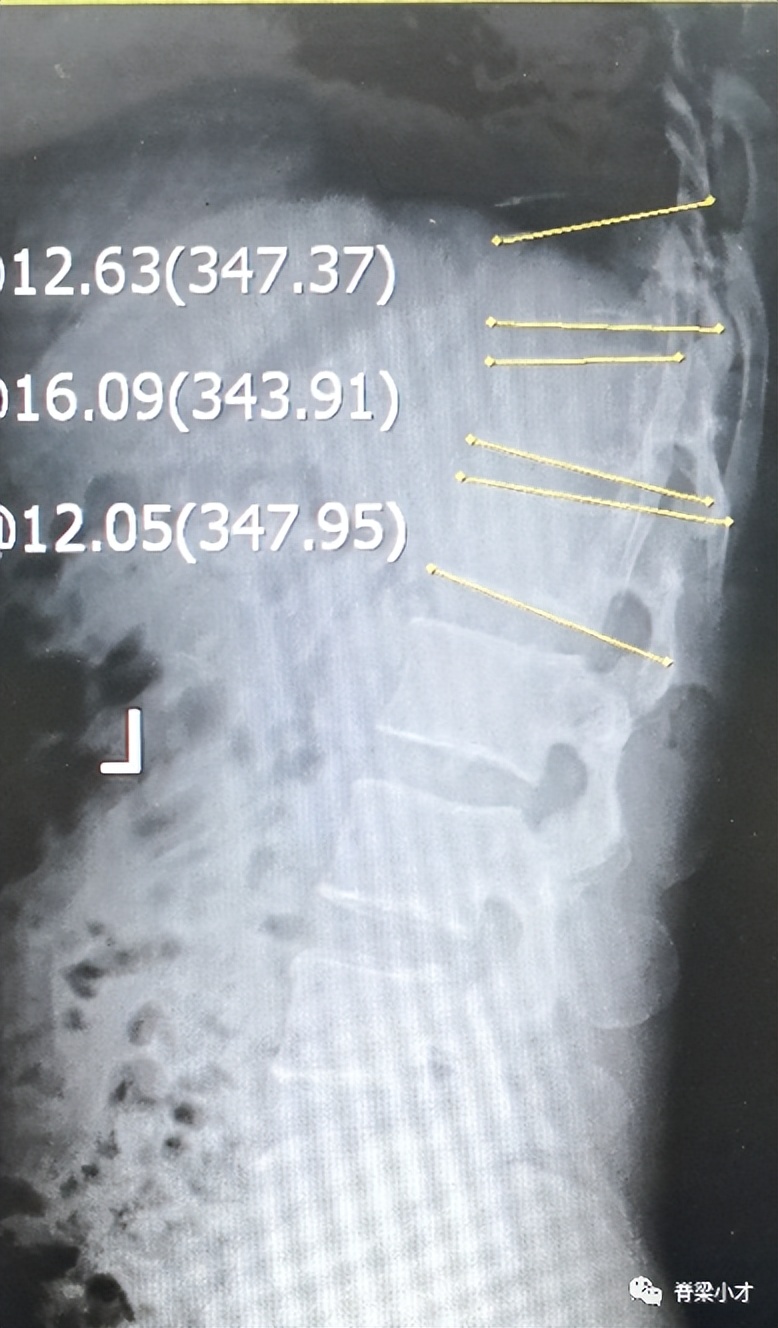

•腰椎休门病

休门病(Scheuermann’s disease)是青少年脊柱后凸的最常见病因,本病有家族性发病倾向,其遗传方式尚不明确,最新研究与COL9A3基因突变有关。近百年来人们对休门病的认识不断深入,但仍有不少尚待明确的问题。文献报告的患病率在1~8%不等,10~11岁之前几乎不会发现,12~13岁后可出现影像学改变。

腰背疼痛是最主要的症状,一般成年后可缓解。诊断主要通过医生查体并最终经X线检查确诊,典型诊断标准是在X片上连续3个椎体大于5°的楔形变,常存在许莫结节、终板不规则、椎间隙狭窄、椎体前后缘骨骺离断、椎间盘退变等。非典型休门病”的诊断存在争议;Blumenthal诊断标准:CT检查椎间隙狭窄、许莫结节和终板不规则3项中2项或核磁显示椎间隙狭窄、许莫结节、终板不规则、椎体楔形变和椎间盘信号减低5项中的3项即可诊断。有人将腰椎有此改变的称之为“腰椎休门病”。腰椎间盘突出症与腰椎休门病关系密切,腰椎休门病可能参与了腰椎间盘突出症的发病。